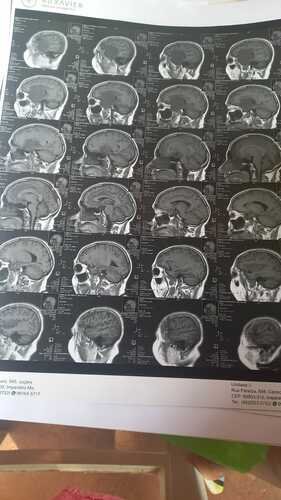

Recentemente, Maria do Socorro recebeu o diagnóstico devastador de um tumor na cabeça. Esta notícia abalou não só ela, mas todos nós que a amamos e admiramos. No entanto, Maria do Socorro é uma lutadora e está determinada a vencer esse tumor.